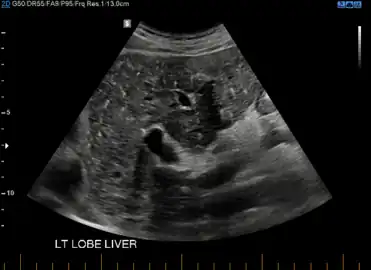

At CT scans, bile duct hamartomas appear as small, well-defined hypo- or isoattenuating masses with little or no enhancement after contrast administration.[4] At MRI, they appear hypointense on T1-weighted images, iso- or slightly hyperintense on T2-weighted images, and hypointense after administration of gadolinium based contrast-agent.[4] On imaging, multiple hamartomas may look similar to metastases or microabscesses.

von Meyenburg Complex in ultrasound. Numerous little cysts with ringdown artefacts.